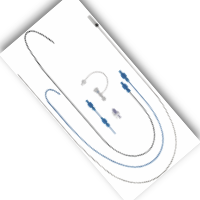

Delivery (Sistema de Entrega)

Two different sheath lengths are available for adults and paediatric patients.

The anti-kink delivery system is also available for VSD occluders.

The delivery system includes: Loader (1), Sheath (1), Dilator (1), Push Cable (1), Y-Connector with extension (1)

A: Long sheath

B: Dilator

C: Push cable

D: Y-connector with tube